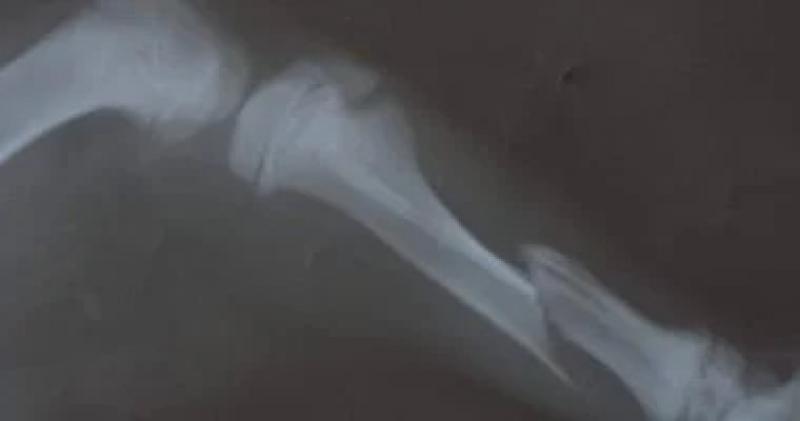

تمكن فريق من أطباء مركز طب وجراحة الحيوانات الأليفة بمديرية الطب البيطري في الغربية، من إجراء عملية لإعادة تثبيت كسر بعظام الساق اليمنى لكلب بعمر 3 أشهر نتيجة تعرضه لحادث سيارة.

وتم استقبال الكلب في العيادة وتبين إصابته بكسر في عظام الساق اليمني بعد تعرضه لحادث سيارة.

وقام بإجراء العملية الفريق المكون من الدكتورة سحر الشافعى، والدكتورة مروة نافع، والدكتور محمد الخولى، ويتم المتابعة والتأكد من استقرار الوضع الصحي للحالة بعد العملية الجراحية وتقديم العلاج اللازم مع توقعات بعودته إلى حياته الطبيعية والتعافى في وقت قريب.